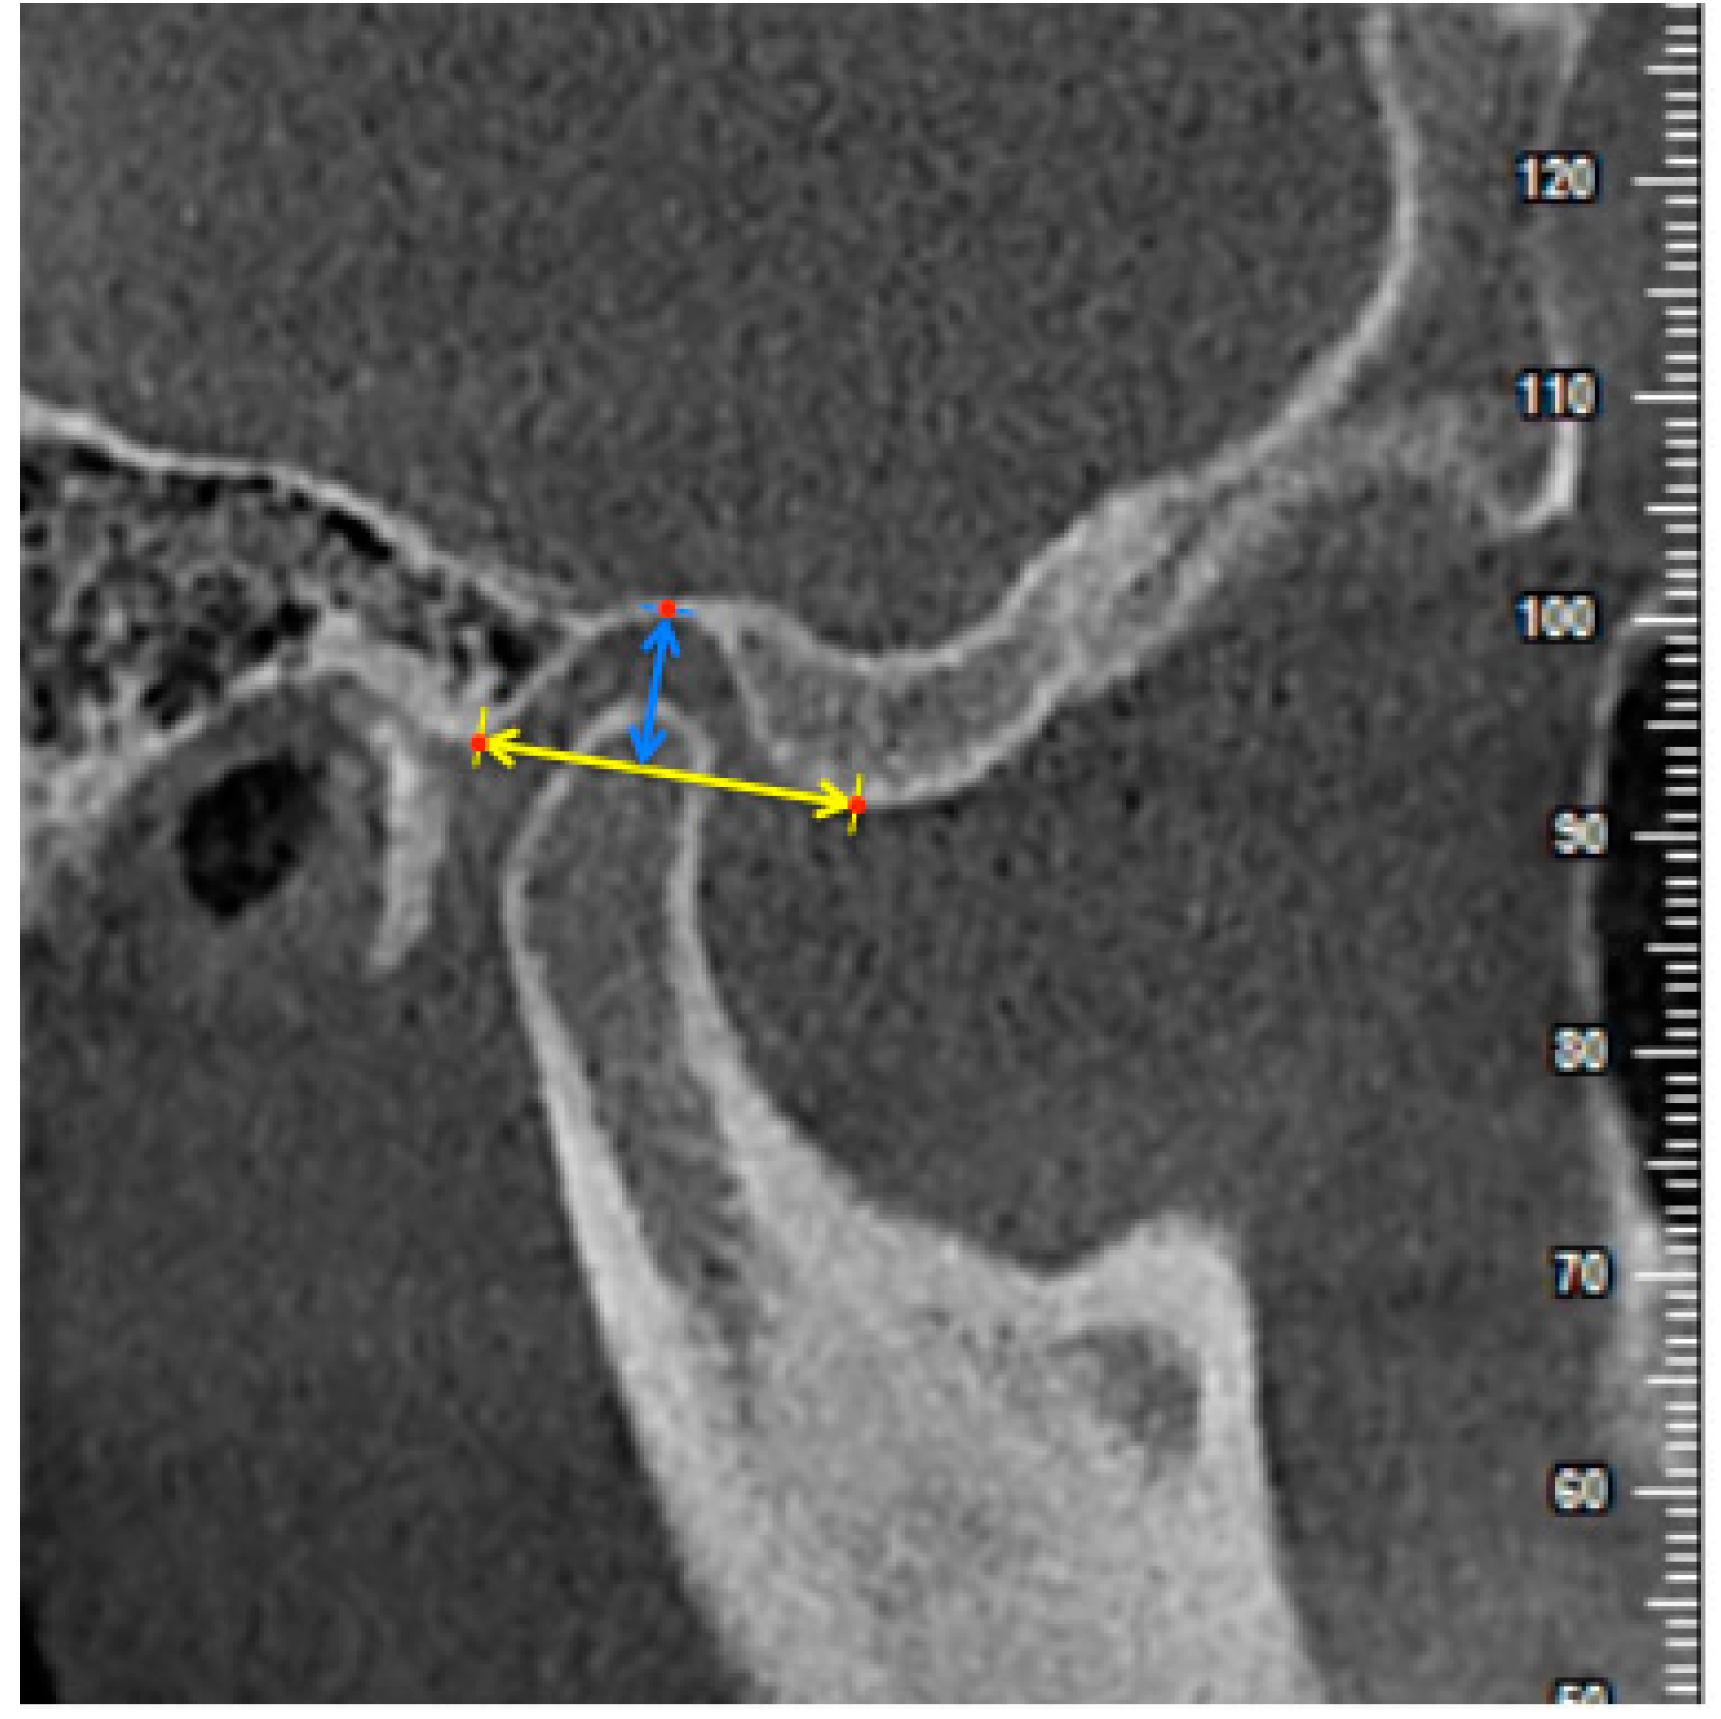

2.4. Measurements